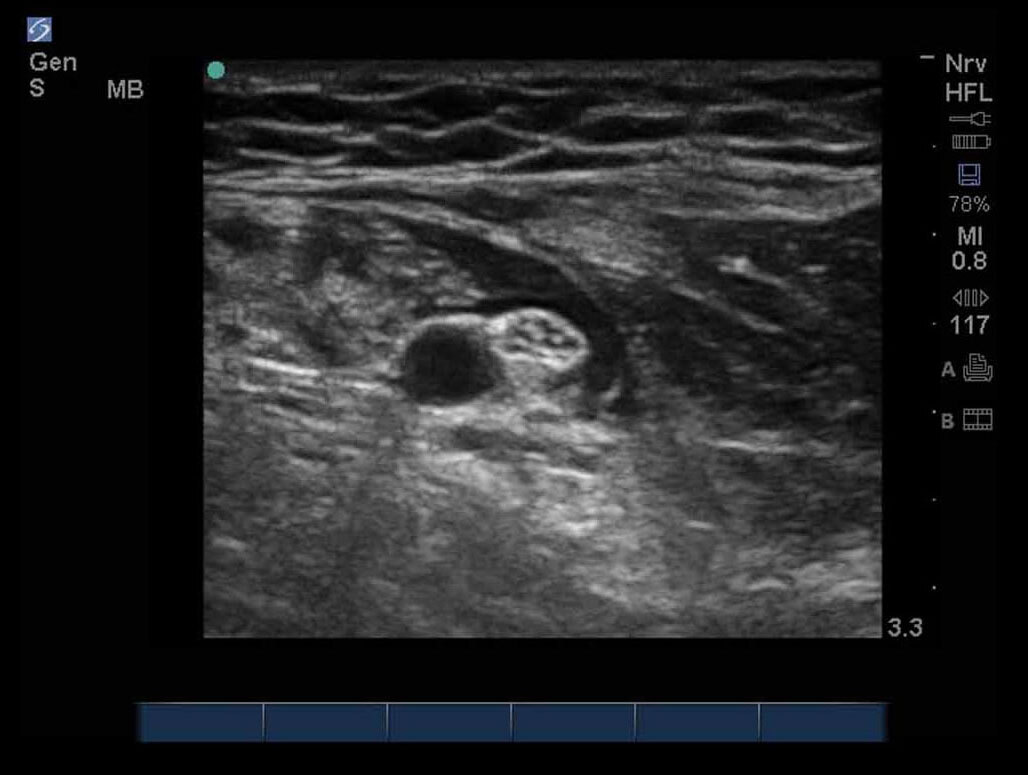

正中2神経注入後の画像

M-Turbo: 正中2神経注入後。